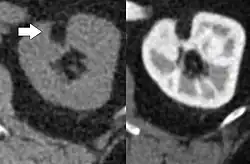

Three methods of scanning can detect angiomyolipomas: ultrasound, computed tomography (CT), and magnetic resonance imaging (MRI).[5] Ultrasound is standard and is particularly sensitive to the fat in angiomyolipomas, but less so to the solid components. However, accurate measurements are hard to make with ultrasound, particularly if the angiomyolipoma is near the surface of the kidney (grade III).[4] CT is very detailed and fast, and allows accurate measurement. However, it exposes the patient to radiation and the dangers that a contrast dye used to aid the scanning may itself harm the kidneys. MRI is safer than CT, but many patients (particularly those with the learning difficulties or behavioural problems found in tuberous sclerosis) require sedation or general anaesthesia, and the scan cannot be performed quickly.[3] Some other kidney tumours contain fat, so the presence of fat is not diagnostic. Distinguishing a fat-poor angiomyolipoma from a renal cell carcinoma (RCC) can be difficult.[6] Both minimal fat AMLs and 80% of the clear-cell type of RCCs display signal drop on an out-of-phase MRI sequence compared to in-phase.[7] Thus, a lesion growing at greater than 5 mm per year may warrant a biopsy for diagnosis.[3]